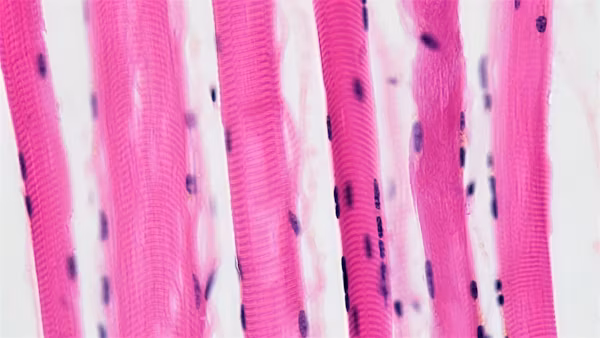

Es seien vier verschiedene Signale möglich, damit der Muskel reagiert, so die Sportmedizinerin. Zum einen könne ein mechanischer Druck ausgeübt werden, denkbar sei hier beispielsweise, wie im Krafttraining, Druck und Zug. Weitere mögliche Signale seien eine vermehrte Durchblutung oder kleine Verletzungen. Es könnten aber auch Stoffwechselsignale oder Nervenimpulse sein, die dem Muskel klarmachen, dass er was zu tun hat. Letztendlich können aber auch lösliche Faktoren wie Hormone und Wachstumsfaktoren eine Rolle spielen.

Essenziell für die Regeneration des Muskels seien die Sattelitenzellen – und nicht nur das. Laut Munz spielen diese auch eine essenzielle Rolle dabei, dass der Muskel größer wird, wenn wir Krafttraining machen. Wenn es nun zu einer kleinen Verletzung in der Muskelfaser kommt, werden die Satellitenzellen aktiviert und können mit sich selbst und anderen Muskelfaserresten fusionieren. Munz unterstrich dabei, dass dies auch bis ins hohe Alter möglich sei. Bisher sei nämlich keine Altersgrenze bekannt, wo Sattelitenzellen nicht mehr aktiviert werden können.

Im Laufe des Vortrags betonte die Sportmedizinerin immer wieder die Kombination aus Ausdauer- und Krafttraining. Die beiden Trainingsarten unterschieden sich sowohl in der Beanspruchung der Muskelfasertypen als auch im Stoffwechsel während des Trainings. Beim Ausdauertraining würden rote Muskelfasern beansprucht und das Training geschehe eher aerob. Anders sehe es bei der anaeroben Trainingsbelastung durch Kraftsport aus, welche die weißen Muskelfasertypen beanspruche.